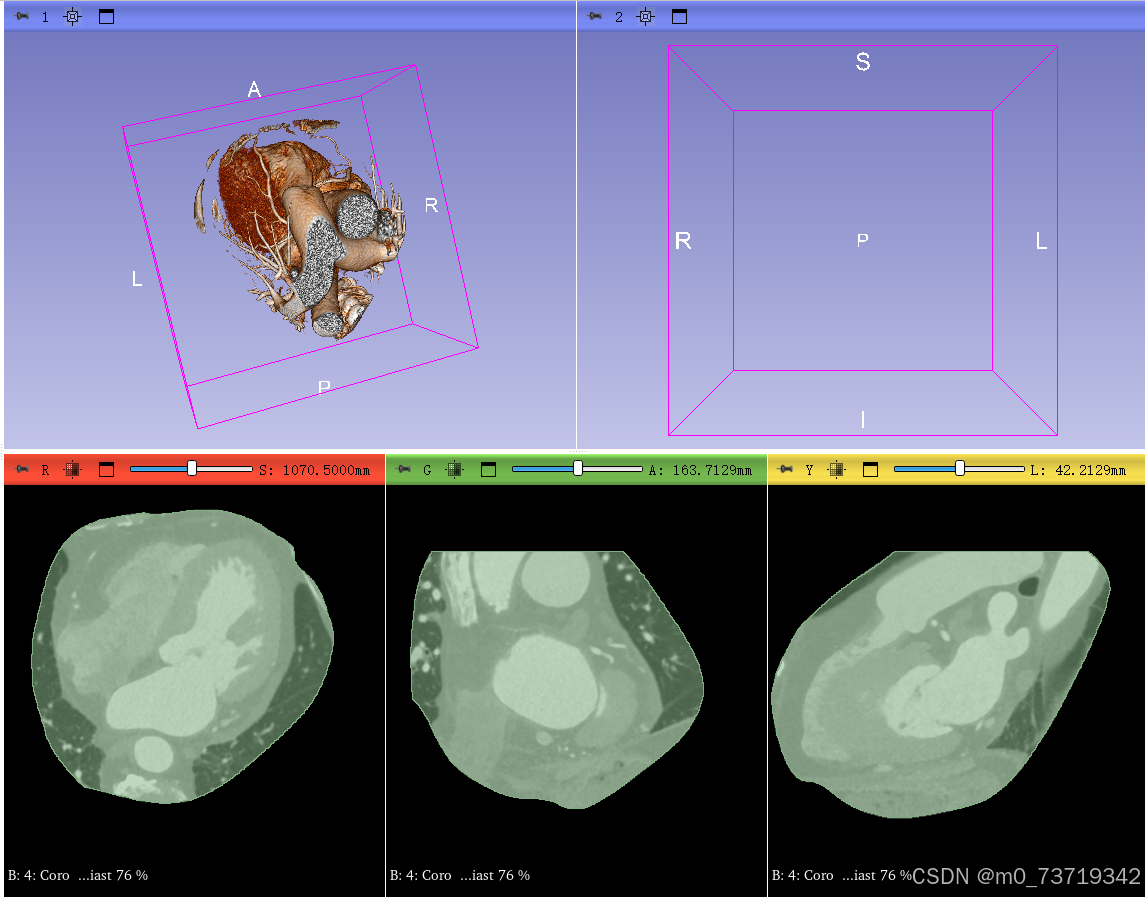

选择病人所有dicom图像(全选快捷键CTRL+A)导入得到如下视图

点击第一个视图显示按钮即可查看三维重建图像

补充:三维视图中如何全方位观看重建图像

鼠标左键拉动以中心轴转动三维图像

鼠标滚轮按住可左右平移图像(同样适用于二维视图)